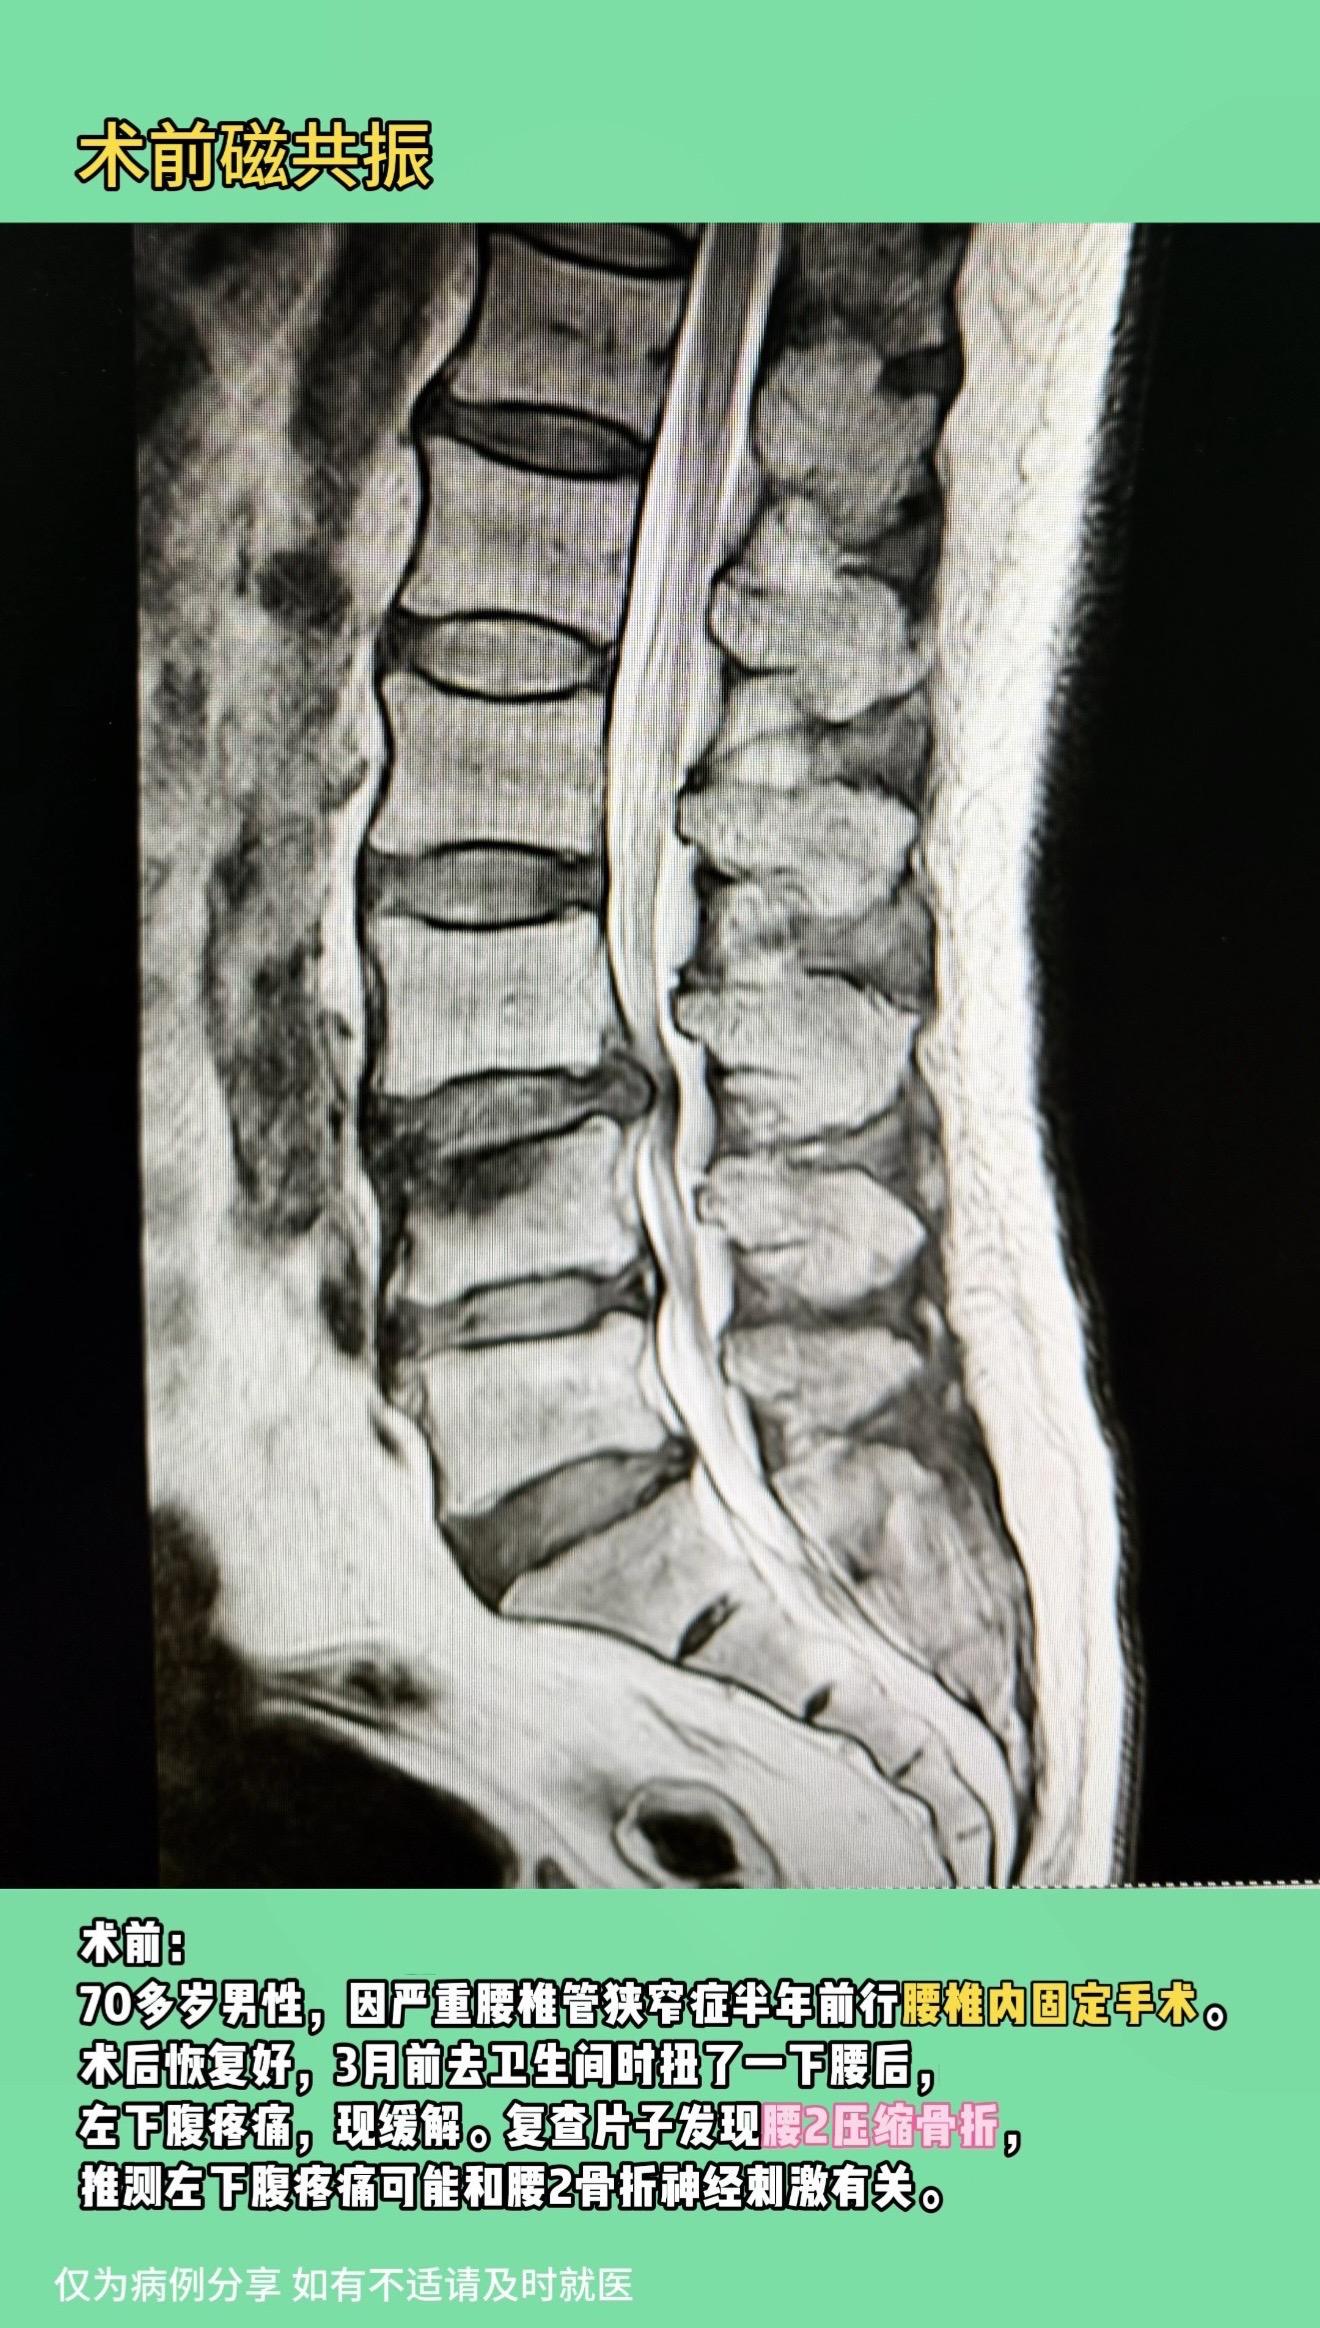

老年腰椎管狭窄症。老年腰椎管狭窄患者越来越多,很多伴有腰椎不稳定需要内固定,但坚强的内固定也带来很多问题,这是摆在患者和医生面前共同的难题。我们该如何选择? 真实病例分享: 70多岁男性,因严重腰椎管狭窄症半年前行腰椎内固定手术。术后恢复好,3月前去卫生间时扭了一下腰后,左下腹疼痛,现缓解。复查片子发现腰2压缩骨折,推测左下腹疼痛可能和腰2骨折神经刺激有关。 再骨折原因:1.坚强内固定上下应力集中;2.老年人骨质疏松,更加重了这种概率。